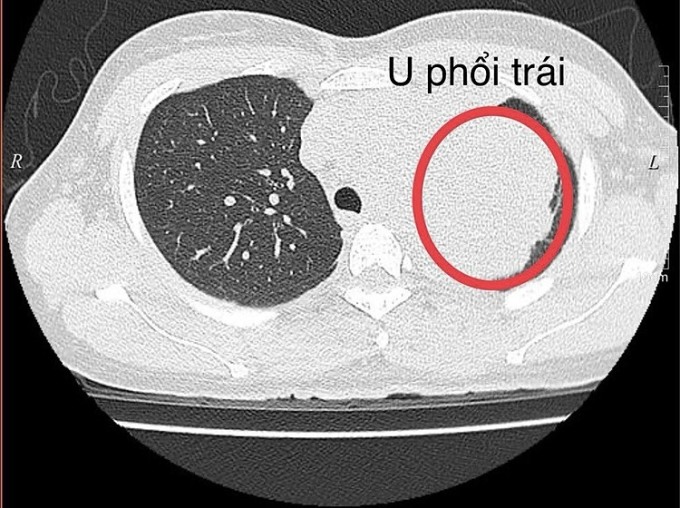

Phú Thọ - Người phụ nữ 34 tuổi đi khám vì đau vai trái âm ỉ ba năm, kết quả chẩn đoán ung thư phổi với khối u dài 12 cm, hiếm gặp.

Ngày 8/4, đại diện Bệnh viện Đa khoa Hùng Vương cho biết bệnh nhân được chụp cắt lớp vi tính, phát hiện khối u thùy trên phổi trái với chiều dài 12 cm, chiều ngang 9 cm. Kết quả sinh thiết ghi nhận khối u ác tính.

Khối u thùy trên phổi trái rất to của bệnh nhân. Ảnh: Bệnh viện cung cấp